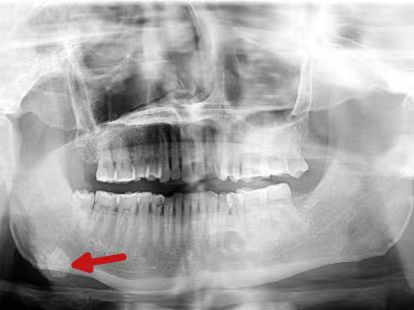

然而,近一个月来,肿痛日益加剧,且口底出现黄白色脓性渗出物,他这才急忙前往医院就诊。接诊医生龙静为谭先生完善检查后发现,他的口底竟藏着一颗约1.2厘米的“石头”,最终确诊为颌下腺导管结石。